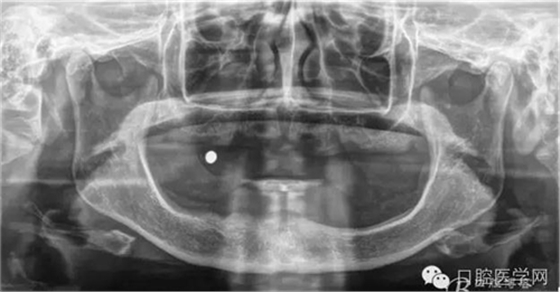

種植覆蓋全口義齒X線顯示骨量條件可以,準(zhǔn)備從下頜兩側(cè)大概3、4的位置植入植體。

種植覆蓋全口義齒判斷位置。